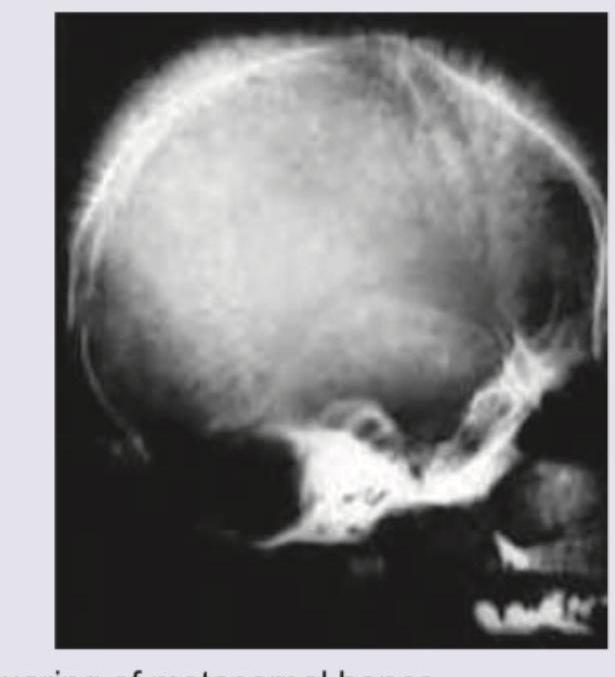

An 8-year-old boy with requirement of multiple blood transfusions. X-ray skull was performed. All are true about the condition shown except:

Explanation: ***Iron chelation leads to bronze diabetes*** - **Bronze diabetes** is caused by **hemochromatosis** (iron overload), where excess iron deposits in the pancreas, leading to diabetes and skin bronzing. Iron chelation therapy is given to **prevent** or treat iron overload, therefore it would logically **prevent** or reverse bronze diabetes, not cause it. - While chronic blood transfusions can cause iron overload, leading to bronze diabetes, chelation therapy is the treatment to prevent this complication and associated organ damage. *Squaring of metacarpal bones* - This is a typical radiological finding in **thalassemia major**, caused by **expanded bone marrow** in response to chronic anemia. - The abnormal erythropoiesis leads to widening of the medullary cavity and thinning of the cortical bone, giving the metacarpals a characteristic rectangular or "squared" appearance. *Erythroid hyperplasia in liver and spleen* - In conditions like thalassemia, the body attempts to compensate for ineffective erythropoiesis by activating **extramedullary hematopoiesis** in organs like the liver and spleen. - This results in the proliferation of erythroid precursors (erythroid hyperplasia) in these organs, contributing to hepatosplenomegaly. *Splenectomy if transfusion requirement increases by 50% over last year* - **Splenectomy** is a consideration in patients with thalassemia who have significantly increased transfusion requirements, usually defined as a 30-50% increase, due to **hypersplenism**. - Hypersplenism leads to increased destruction of red blood cells and premature removal of transfused cells, necessitating frequent transfusions.